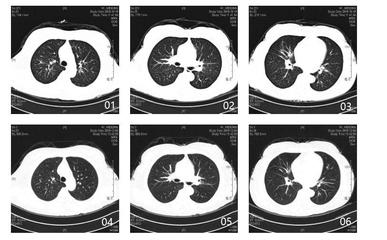

另外,生气的人更容易导致免疫功能低下,免疫功能受损,容易引起肺结节。那么中医如何解决这种“气怒”的肺结节人群呢?分享几个案例。案例1:马先生,65岁,吸烟30多年。2020年7月,因胸闷、胸痛、憋气等症状到医院就诊。CT检查后显示双肺多发结节。左肺下叶胸膜下有较大的实性结节,直径约6 mm,未给予其他治疗。